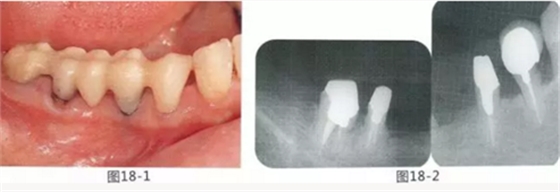

圖18-14 使用圓頭金剛車針進(jìn)行骨外科處理。

圖18-15 使用鎢鋼車針去除殘留在牙根面的纖維。